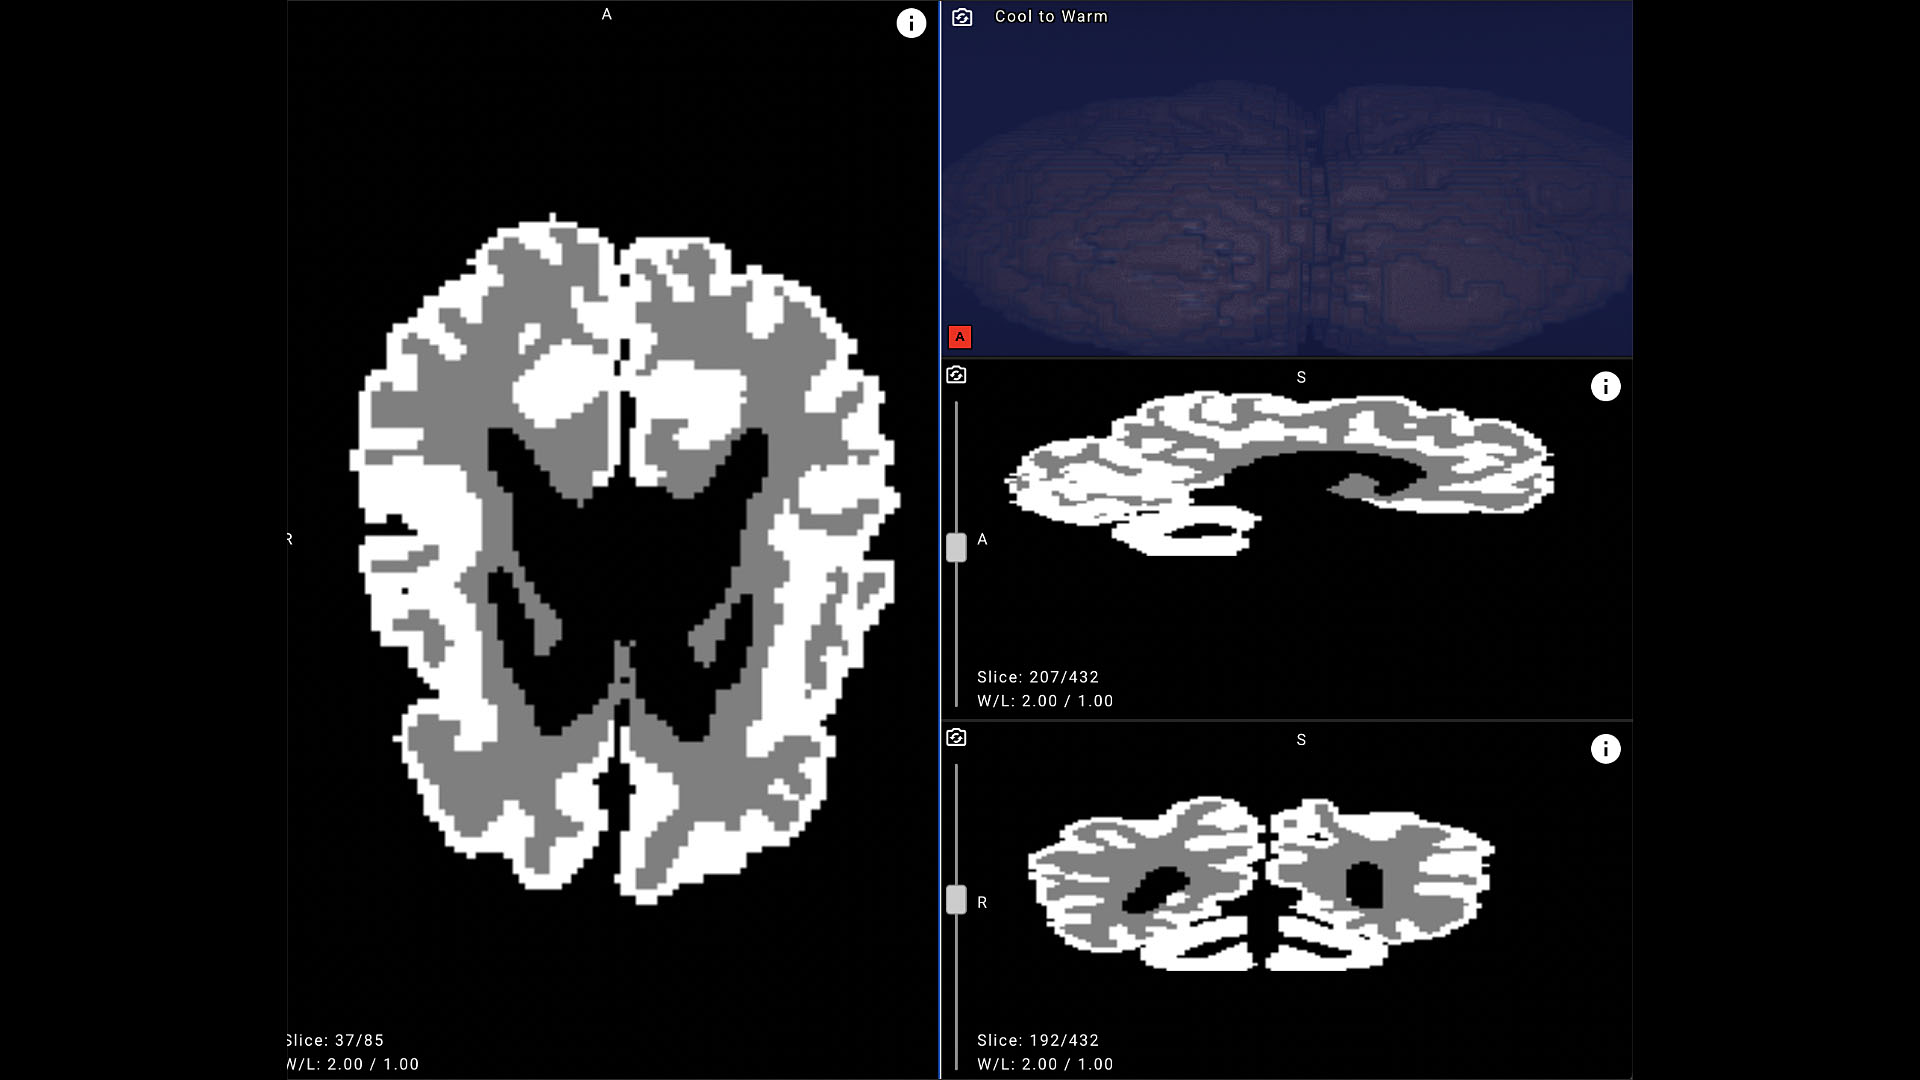

Bu önemli konuda şirketten yapılan resmi açıklama şöyle oldu: “Yandex B2B Tech; Yandex Veri Analizi Okulu ve St. Petersburg Devlet Pediatrik Tıp Üniversitesi iş birliğiyle, 12 aydan küçük bebeklerde beyin gelişimini değerlendiren dünyanın ilk yapay zekâ tabanlı çözümünü geliştirdi. Geliştirilen sinir ağı sayesinde, beyin MR’ı analizleri otomatik olarak yapılıyor ve böylelikle günler süren işlemler sadece birkaç dakikada tamamlanabiliyor. Serebral palsi ve diğer merkezi sinir sistemi hastalıklarıyla ilgili şüpheli durumlarda doktorlara karar desteği sunan bu teknoloji, etkili rehabilitasyon stratejilerinin belirlenmesine önemli katkı sağlıyor. Serebral palsi, genellikle daha anne karnındayken ya da doğumdan kısa süre sonra bebeklerde görülen, beyin dokusundaki kalıcı hasar sonucunda ortaya çıkan ve hareket etme kabiliyetinde azaltan bir hastalıktır.  Serebral palsi, dünya genelinde çocukluk çağında ortaya çıkan engelliliğin başlıca nedenlerinden biri. Dünya Sağlık Örgütü’ne (DSÖ) göre, her 1.000 doğumda tahminen 2–3 çocuk bu rahatsızlıktan etkileniyor. Türkiye’de ise, 2016–2022 yılları arasında 18 yaş altı çocuklar üzerinde yapılan kapsamlı bir araştırmada, görülme sıklığının 1.000 çocukta 7,74 olduğu tespit edildi.

Bu durum, güvenilir ve erken tanı araçlarına ve etkili rehabilitasyon planlamasına olan ihtiyacı ortaya koyuyor. Erken tanı, hastalığın seyri ve etkili bir rehabilitasyon için büyük önem taşıyor. Ancak serebral palsiyi yaşamın ilk 12 ayında saptamak, modern tıbbın en zor alanlarından biri olarak kabul ediliyor. Bebek beyninin olağanüstü hızlı gelişimi ve beyin MR’ında gri ve beyaz madde arasındaki kontrastın düşük olması, yani beynin korteksini oluşturan ve üst düzey işlevleri sağlayan dokuların birbirinden zor ayırt edilmesi, tanı sürecini oldukça güçleştiriyor. Bir beyin MR’ı çekimi genellikle 20 ila 40 dakika sürse de elde edilen görüntülerin yorumlanıp raporlanması deneyimli bir radyolog için bile birkaç saatten birkaç güne kadar uzayabiliyor. Özellikle hastalığın seyrini izlemek için yapılan uzun süreli takiplerde, hekimlerin çok sayıda MR görüntüsünü değerlendirmesi gerektiğinden iş yükü ve sonuçların alınma süresi belirgin şekilde artıyor.

Bu alandaki zorlukları aşmak için araştırmacılar daha önce de yapay zekâdan faydalanmaya çalıştı; özellikle makine öğrenimi yarışmaları bu konuda önemli bir rol oynadı. Örneğin, 2019 yılında düzenlenen MICCAI Grand Challenge yarışmasında, katılımcılardan iSeg-2019 veri setini kullanarak altı aylığa kadar olan bebeklerin beyin MR görüntülerini bölümlendirmeleri istendi. Yarışma, dünyanın dört bir yanından geliştiricileri bir araya getirdi ancak önemli bir sorunu da ortaya çıkardı: Açıklanabilir veri eksikliği. Özellikle, klinik kullanım amacıyla yapay zekâ modellerini eğitmek için gerekli olan gri ve beyaz maddenin ana hatlarını gösteren segmentasyon maskeleri çok azdı. iSeg-2019 veri seti sadece 15 açıklamalı görüntü içerirken, üniversitenin arşivinde 1500 hastanın açıklaması olmayan MRI taramaları bulunuyordu. Bu eksikliği gidermek amacıyla Yandex araştırmacıları, tıp uzmanlarıyla birlikte yeni açıklamalar oluşturdu, özel bir sinir ağı mimarisi geliştirdi ve kapsamlı makine öğrenimi deneyleri yürüttü. Sonuçta ortaya çıkan model, yapılan iç değerlendirmelerde bebek beyinlerinde gri ve beyaz maddeyi ayırt etmede yüzde 90’ın üzerinde bir doğruluk oranına ulaştı ve klinik uygulamalar için güçlü bir potansiyel sergiledi.